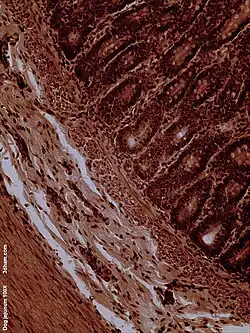

Histology

The jejunum contains very few Brunner's glands (found in the duodenum) or Peyer's patches (found in the ileum). However, there are a few jejunal lymph nodes suspended in its mesentery. The jejunum has many large circular folds in its submucosa called plicae circulares that increase the surface area for nutrient absorption. The plicae circulares are best developed in the jejunum.

There is no line of demarcation between the jejunum and the ileum. However, there are subtle histological differences:

- The villi of the jejunum look like long, finger-like projections, and are a histologically identifiable structure.

Dog jejunum (magnified 100-fold)

Dog jejunum (magnified 100-fold)